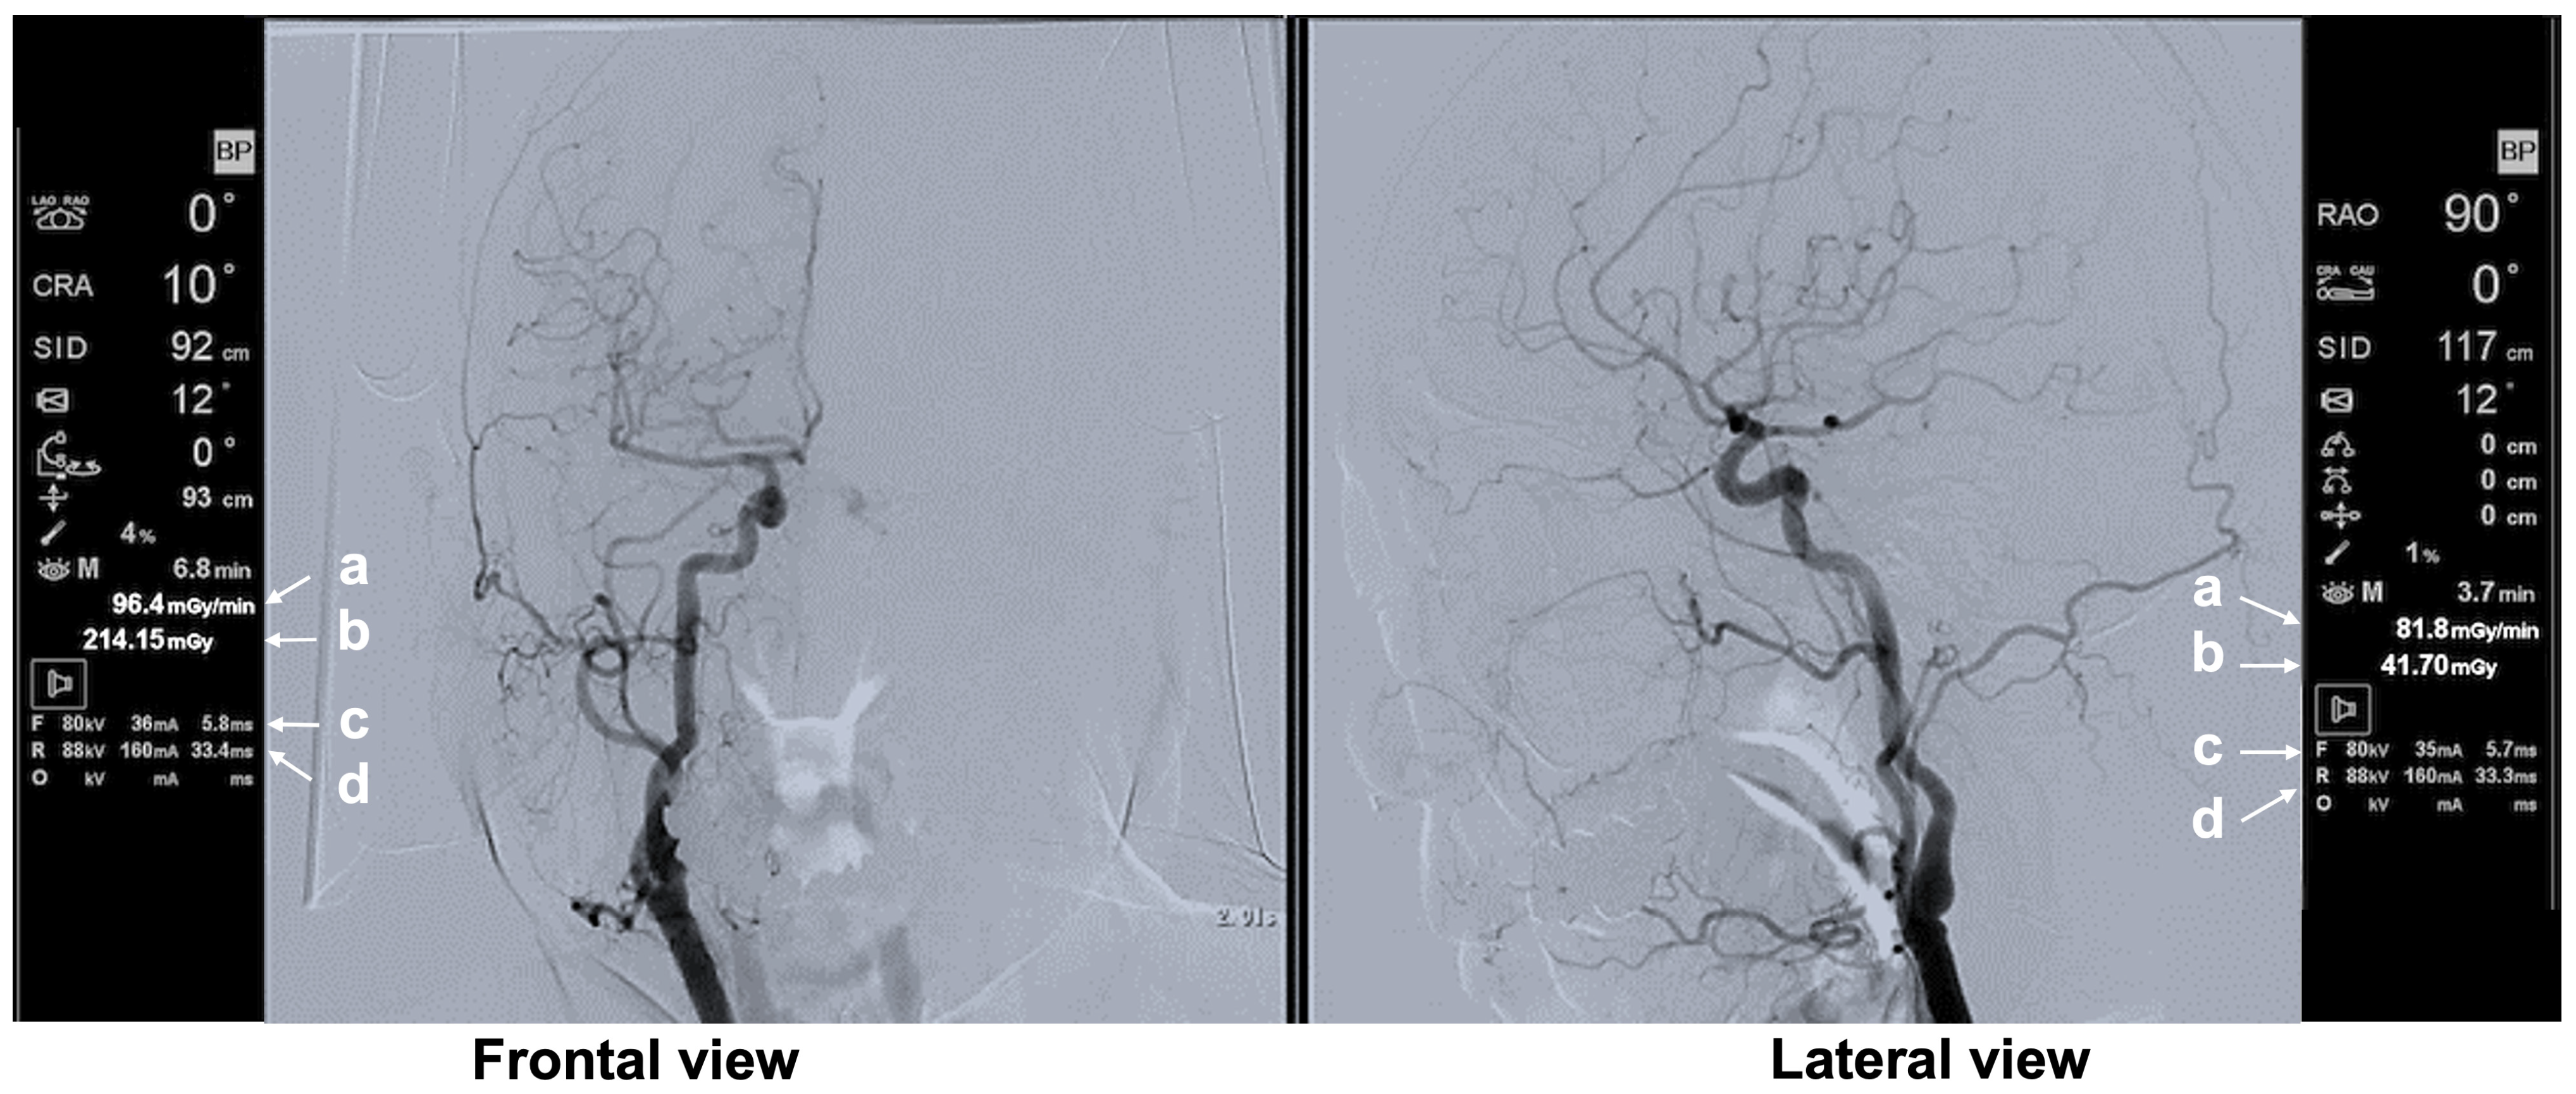

3.3.3. Typical Scene 3 (Case 3)

| Typical Scene No. | Case No. | DSA Site | X-Ray Projection | FPD Size (inch) | SID (cm) | Ka,r (mGy) | Table Height (cm) | Cervical Unprotected Dose Rate (mSv/h) | Chest Unprotected Dose Rate (mSv/h) | Cervical/Chest Unprotected Dose Rate Ratio |

|---|---|---|---|---|---|---|---|---|---|---|

| 3 | 3 | Lt C-CAG | Frontal—LAO 0°, Cranial 1° | 12 | 90 | 80.06 | 93 | 0.48 | 1.65 | 0.29 |

| Lateral—RAO 90°, Cranial 0° | 12 | 111 | 100.1 | |||||||